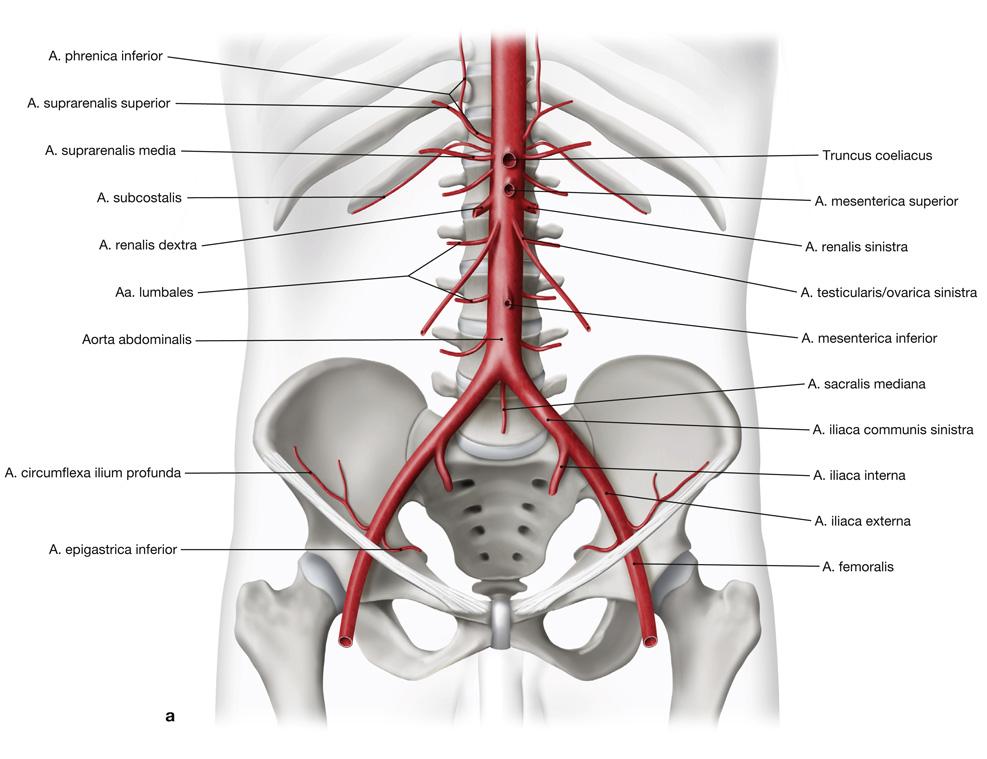

Fig 3.21: Aorta abdominalis

|